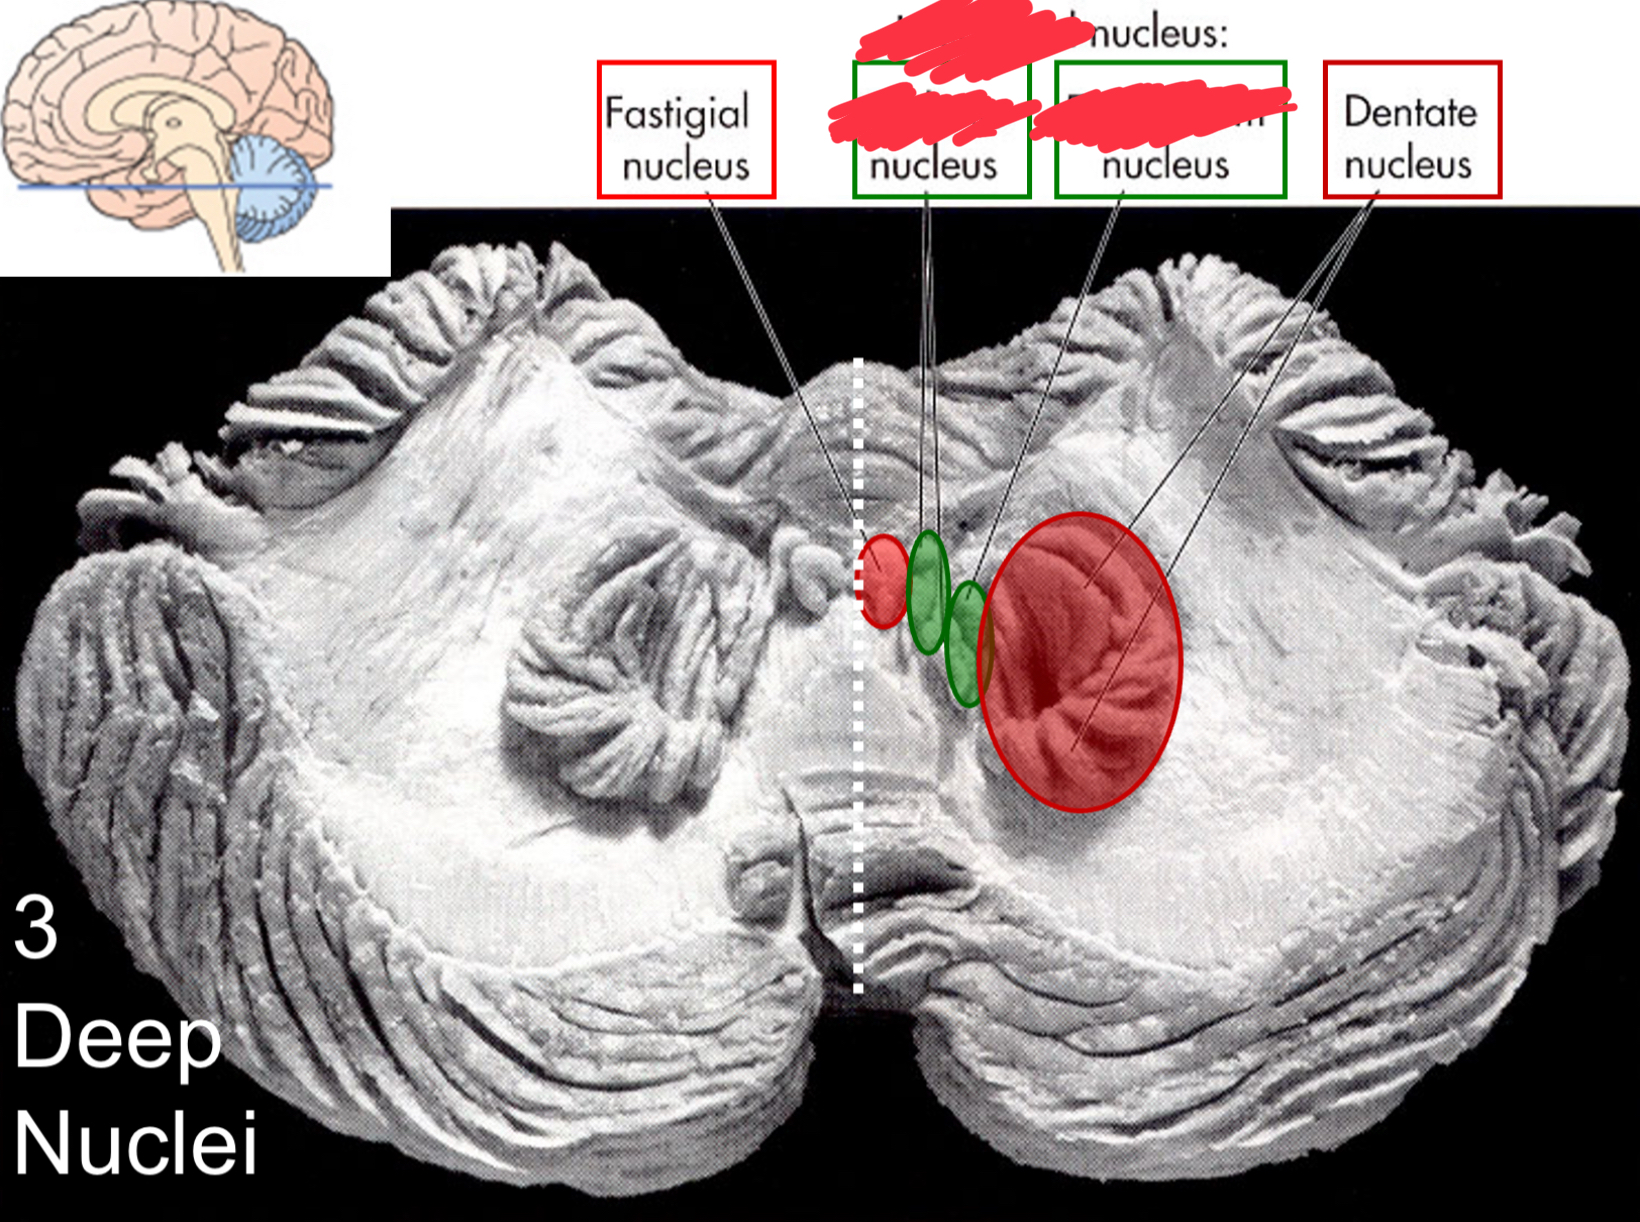

fastigial nucleus

interposed nucleus (globose + emboliform)

dentate nucleus